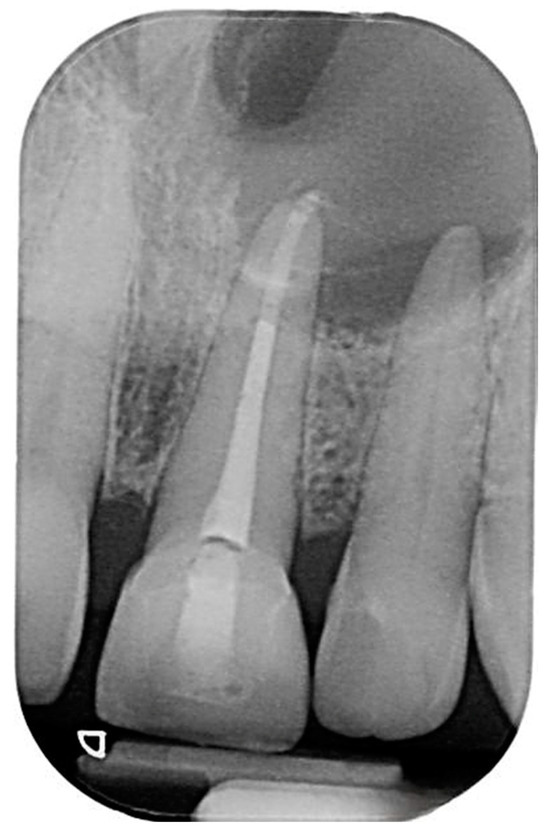

2. Case Presentation

2.1. Chief Complaints History and Clinical Findings

2.2. Delivery of Treatment

2.4. Healing of the Defect and Follow Up